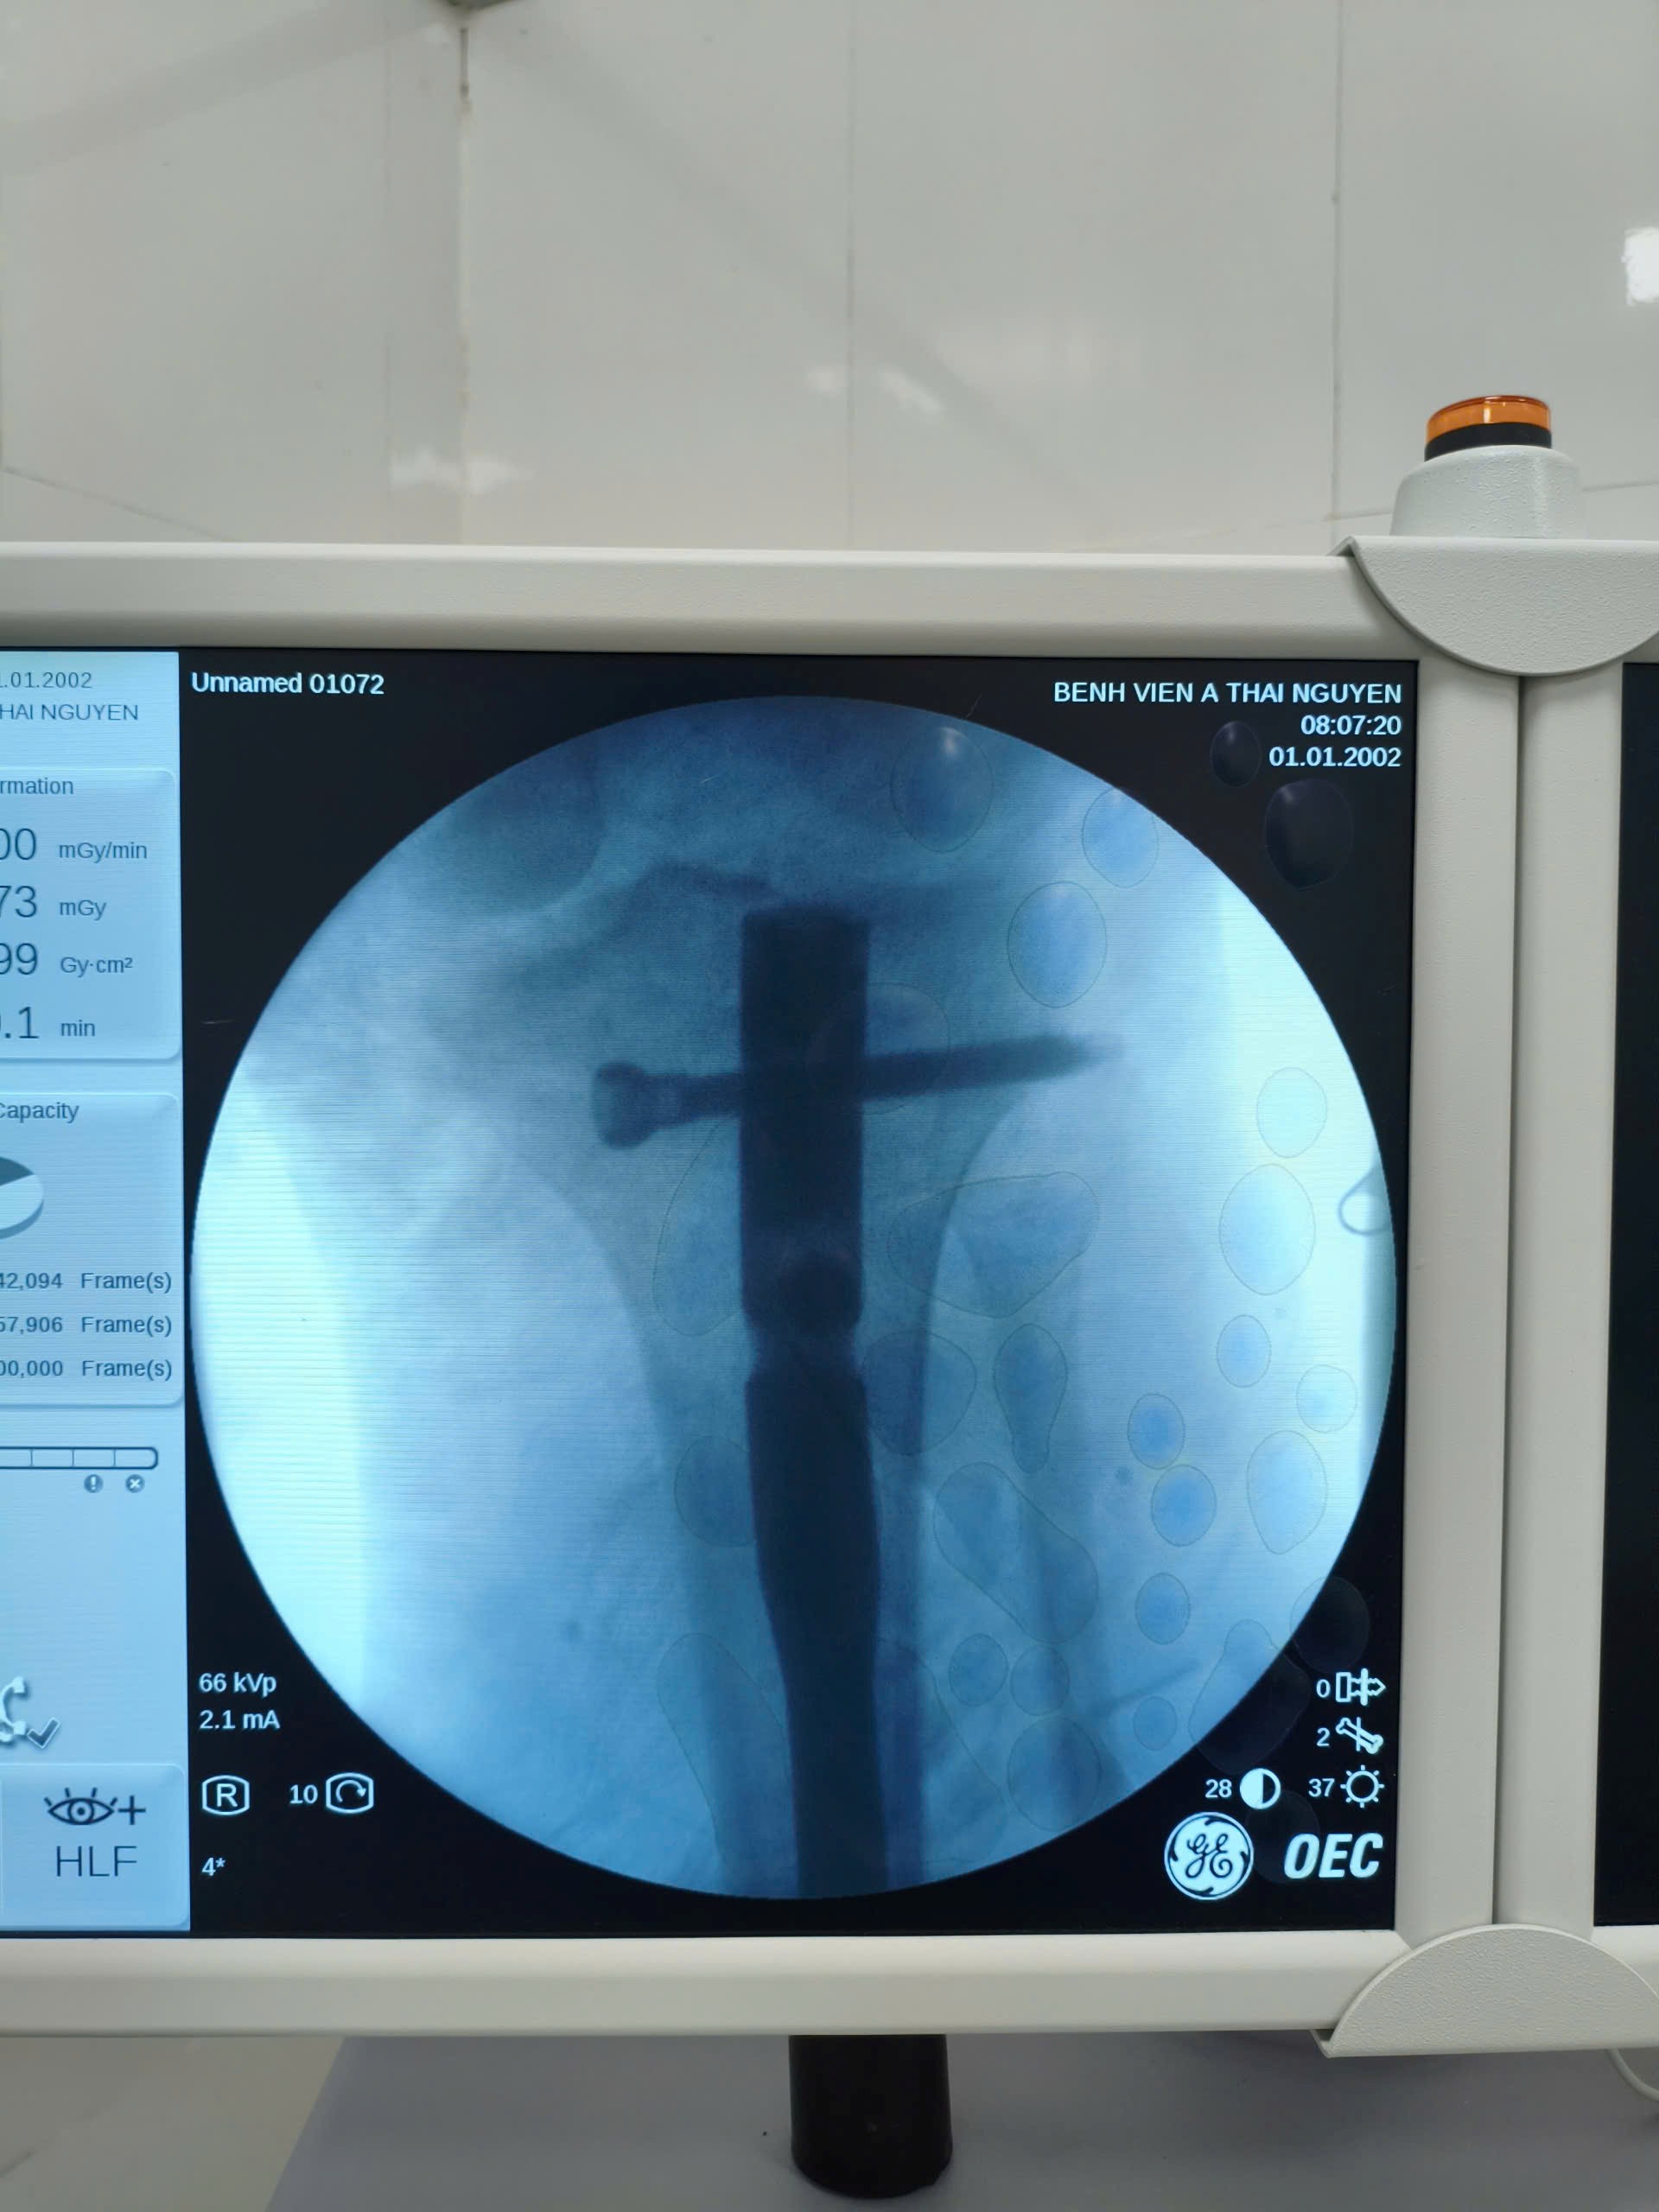

Phẫu thuật kết hợp xương trên màn hình tăng sáng cho bệnh nhân tại Bệnh viện A.

Theo BSCKI. Vũ Đình Linh – Khoa Ngoại chấn thương, Bệnh viện A: “Việc sử dụng máy C-arm trong phẫu thuật kết xương giúp bác sĩ kiểm soát việc nắn chỉnh đường gãy xương về giải phẫu mà không cần mổ mở ổ gãy (một dạng giống như mổ nội soi); mang lại hiệu quả cao trong các ca phẫu thuật khó, phức tạp và chuyên sâu bệnh nhân sẽ không còn phải chuyển tuyến trên nhờ đó giảm chi phí rất lớn cho người bệnh.  Với sự hỗ trợ của máy C-arm thời gian phẫu thuật được rút ngắn, giảm mất máu, hạn chế những tai biến có thể xảy ra, thời gian liền xương nhanh, người bệnh sớm phục hồi và trở lại với sinh hoạt bình thường.